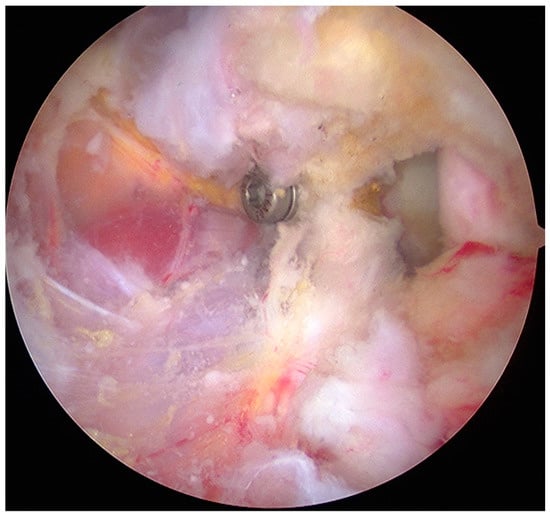

- The graft was positioned on the anterior glenoid neck with the switching stick through the posterior portal (Figure 3).

- The graft was fixed. Two holes were made through the coracoid and the glenoid using the double cannula. Graft trimming was performed with the burr (Figure 4).